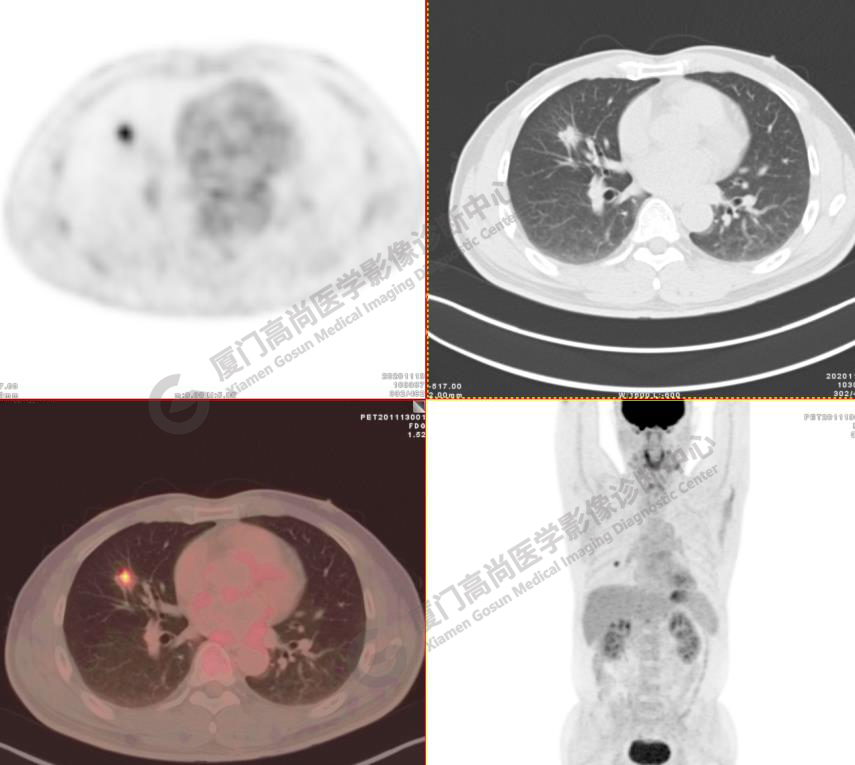

病例1:某男士,52歲,2020年11月體檢,CT發(fā)現(xiàn)右肺中葉結(jié)節(jié)影,查血腫瘤標(biāo)記物正常。

右肺中葉見一混雜密度磨玻璃結(jié)節(jié),大小約1.8x1.5cm,密度不均勻,以實(shí)性密度為主,邊緣可見分葉、毛刺,水平裂牽拉凹陷,F(xiàn)DG攝取增高,SUVmax4.7,肺門、縱隔未見FDG高攝取淋巴結(jié), 未見遠(yuǎn)處轉(zhuǎn)移征象。

影像診斷:右肺中葉浸潤(rùn)性腺癌。(TNM分期 T1bN0M0 ⅠA2期)

病理診斷:浸潤(rùn)性腺癌